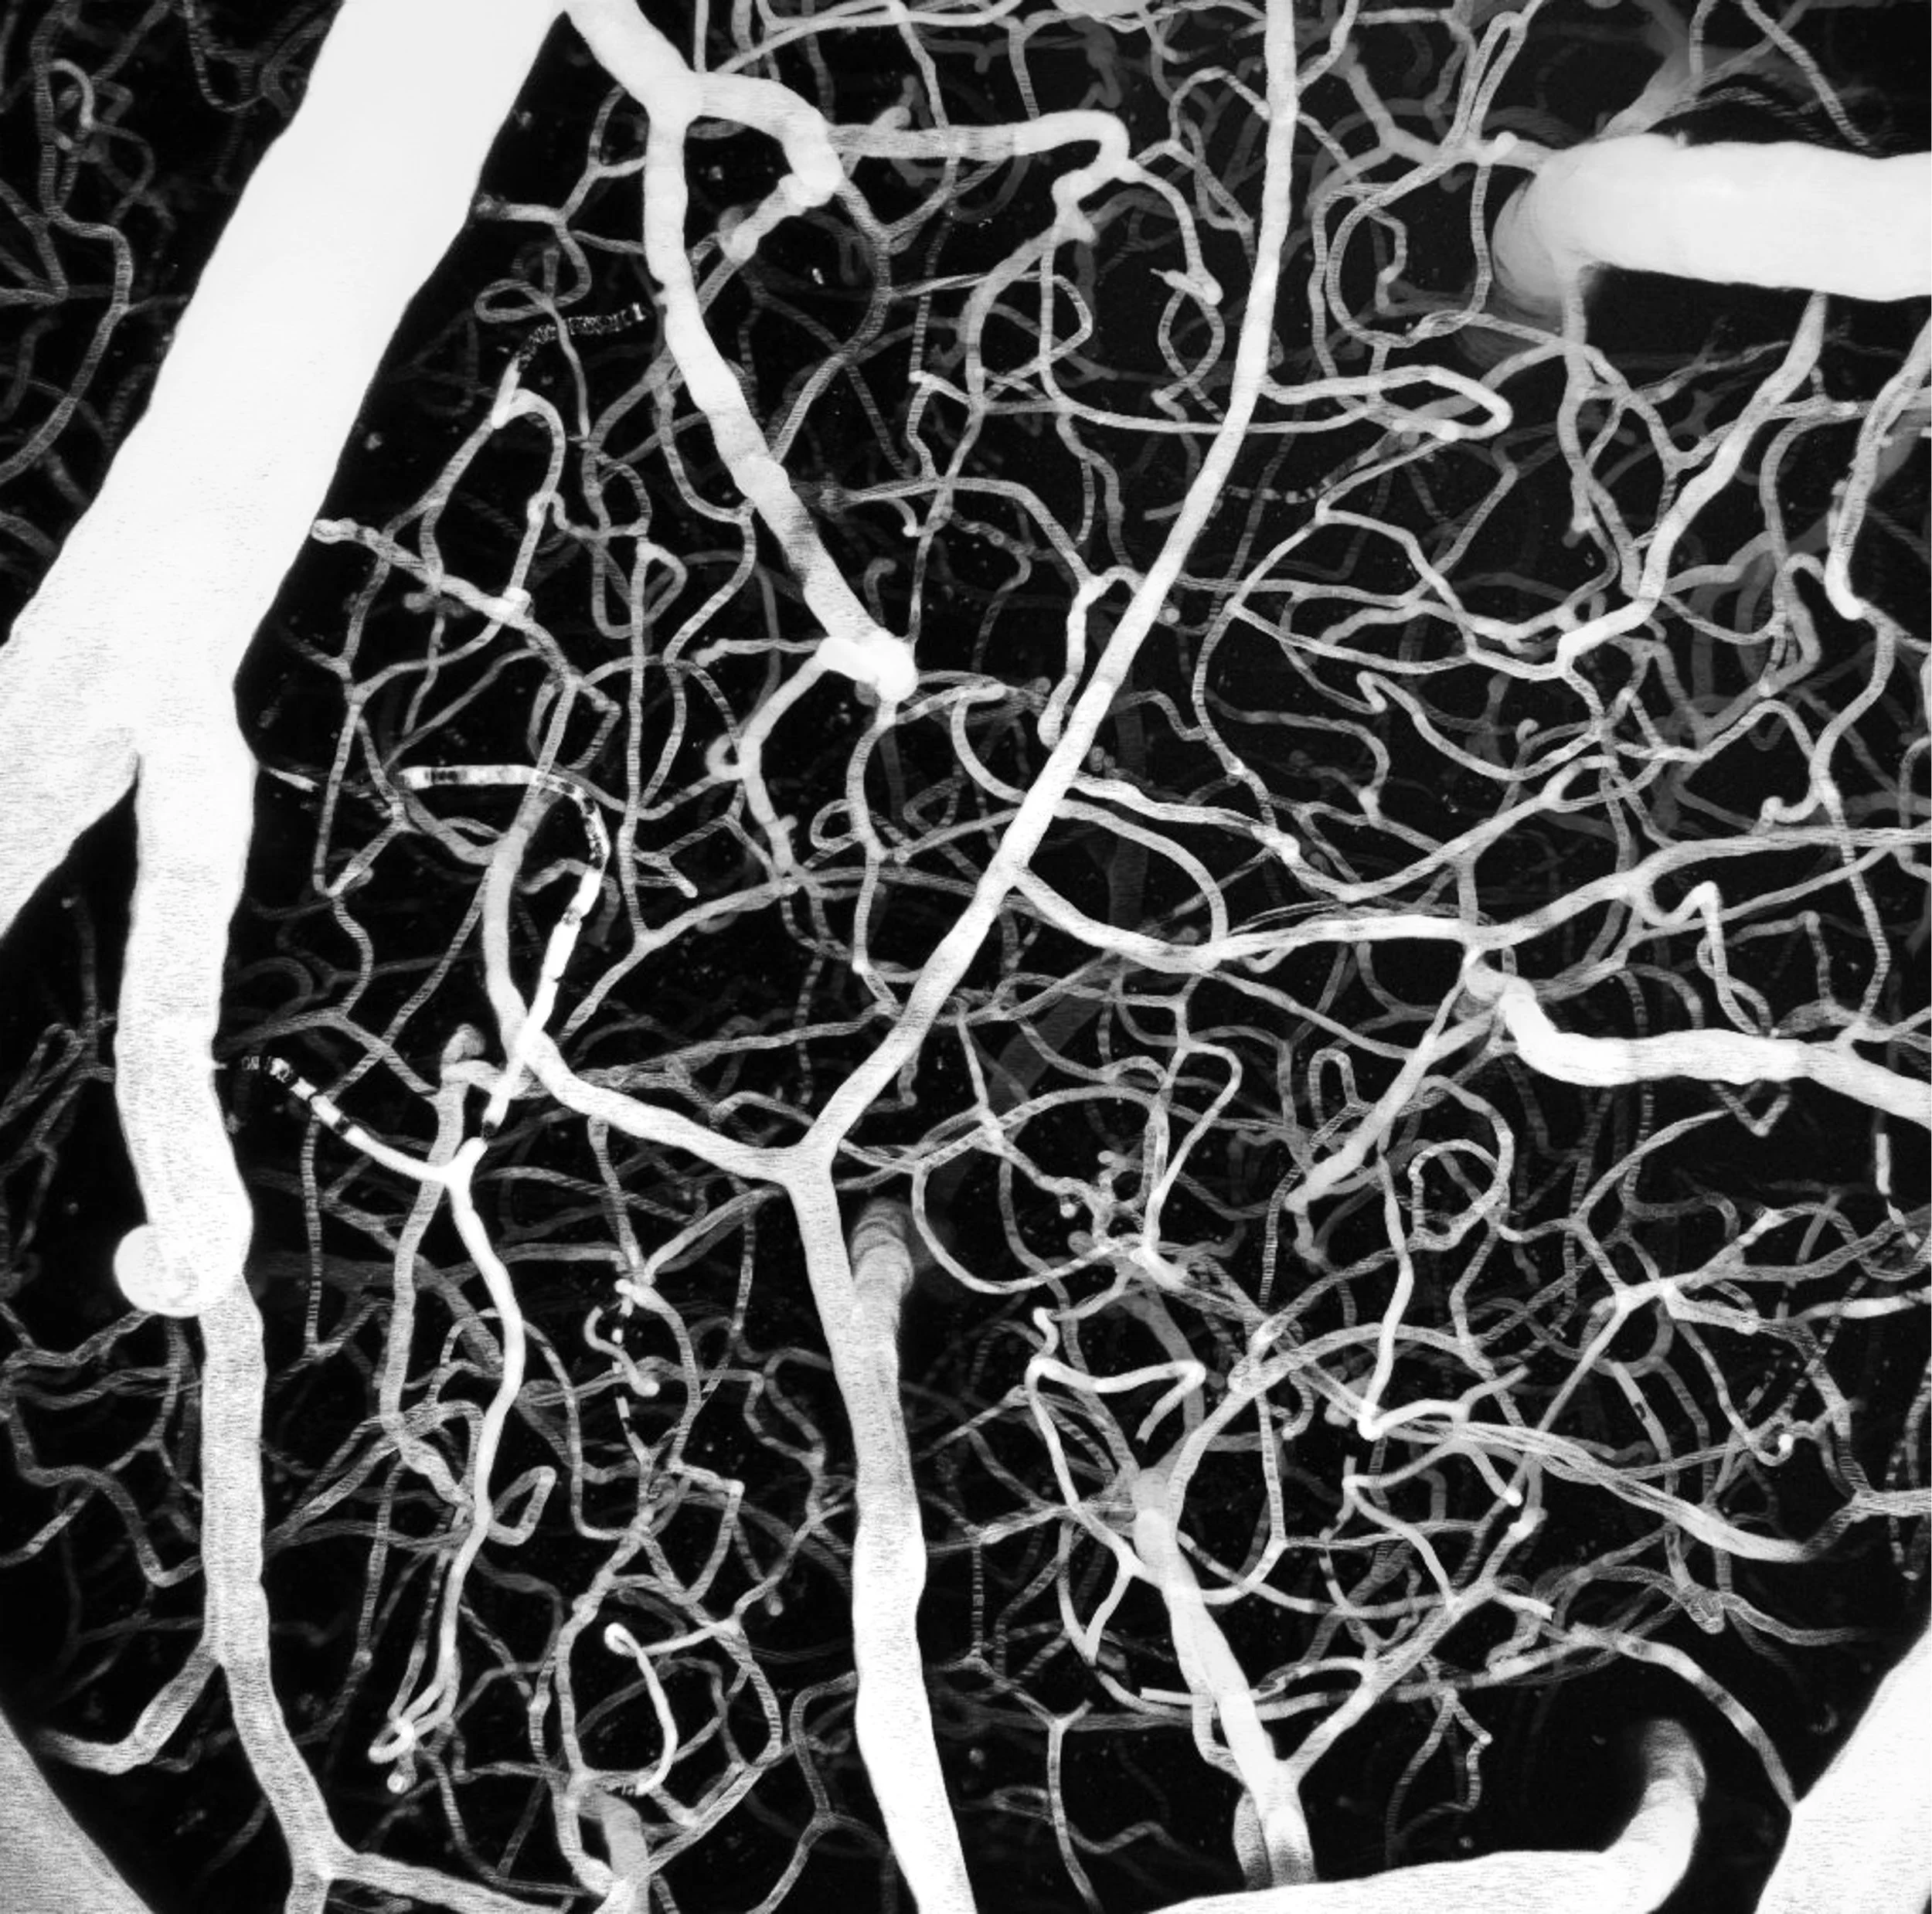

Our research focuses on vascular ion channels and signal transduction pathways. To investigate how they impact blood flow control, we use different imaging techniques, electrophysiology and genetically-engineered mouse models.

Our investigations span the full spectrum from the single molecule level to the whole in vivo level. The major goal of our research is to understand vascular signaling, blood flow control and the changes associated with small vessel and neurodegenerative diseases as well as aging.

Neurovascular coupling and Cerebral blood flow regulation